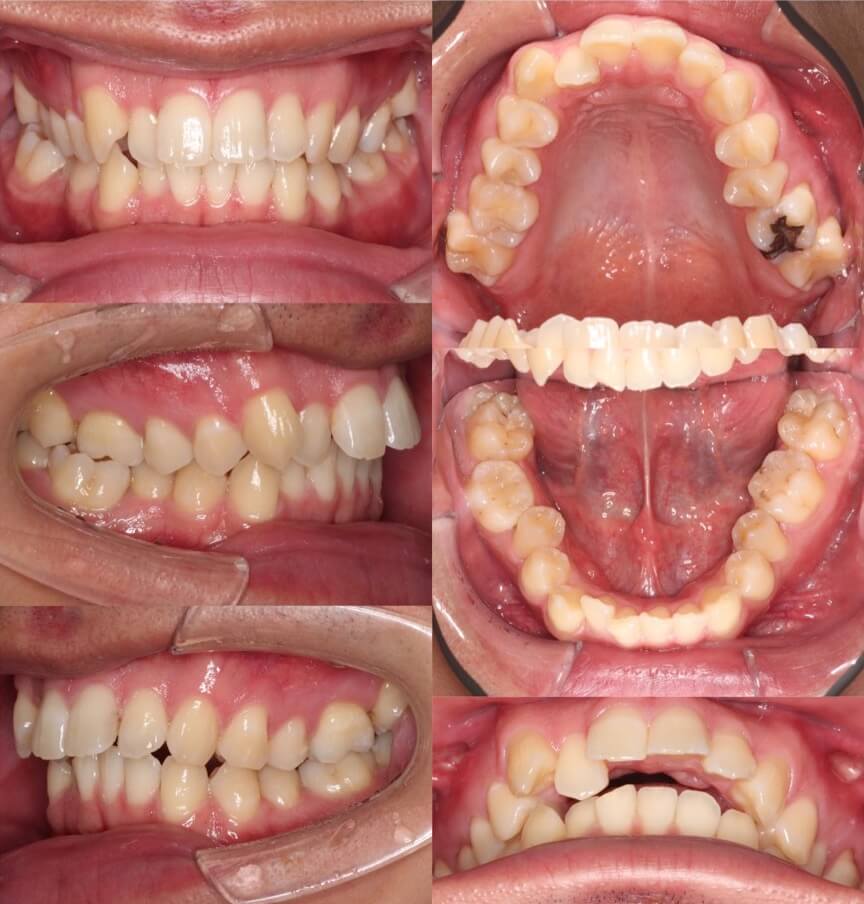

高校生女性・マウスピース型装置・遠心移動

途中で、右下前歯がアンフィットしてしまったため、フックを設置しマウスピースを覆うようにゴムをかけてリカバリーを行いました。お住まいが遠方になってしまい、中々通院回数を確保する事ができなかったのですが、何とか治療を終了する事ができました。

<症例概要> 難易度★★☆☆☆

主訴:出っ歯

年齢・性別:高校生女子

住まい:千葉県八千代市

症状:上顎前突・叢生

治療方針:上顎後方移動・ストリッピング

治療装置:マウスピース型矯正装置(アライナー装置)

治療期間:1年10か月(1週間交換)

アライナー枚数:60+29ステージ

リテーナー:上下クリアタイプ+上フィックスタイプ

治療費用:990,000(税込)

代表的副作用:痛み・治療後の後戻り・歯根吸収・歯髄壊死・歯肉退縮